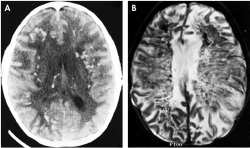

The recent FDA alert concerns a serious adverse effect of rituximab in patients with systemic lupus erythematosus-an unapproved, off-label use. Two patients developed progressive multifocal leukoencephalopathy, a fatal viral infection of the central nervous system caused by reactivation of a virus commonly present in most people and harmless except in the immunocompromised. (See Figure 1, above right.)

Figure 1 - Click to enlarge in new windowFigure 1. Progressive Multifocal Leukoencephalopathy